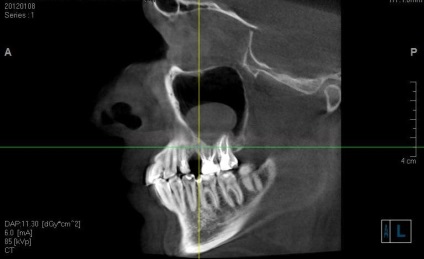

A fő kutatás módszere a feltétele az arcüreg is egy X-ray, és a rendes vetülete (kétdimenziós) képeket, itt az ideje elfelejteni. Megbízhatósága és pontossága csak 25-30%.

Diagnózis a odontogenikus ciszták szükségképpen leolvasó, lehet, hogy egy multislice vagy, megint csak a kúp nyaláb tomográfia. A beolvasási terület kapjon a középső és felső harmadában az arc.

Meg kell jegyezni, hogy még a legkifinomultabb módszereit sugárzás kutatás nem zárja ki, hogy szükség van az ellenőrzés. Ellenőrzés sinus feltárja a legapróbb szöveti változásokat és funkcionális károsodás, hogy nem áll rendelkezésre más módszerekkel. Különösen csak felmérés pontosan meg tudja határozni, hogy a tartalom telt ciszta, a zóna a felerősítését, és így tovább.